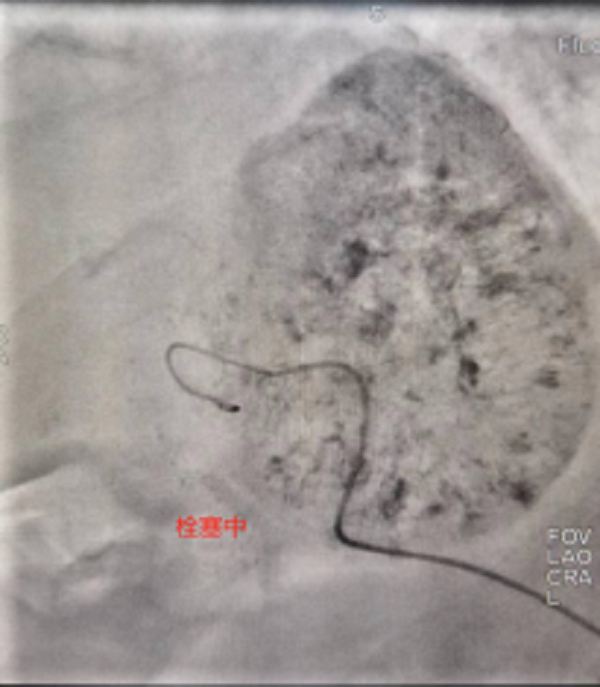

此次来院检查腹部增强CT提示:肝右叶占位性病变,考虑为原发性巨块肝癌,肿瘤大小达到60mmx84mm。患者之前已进行过结肠癌根治性右半结肠切除+胆囊切除术,病情复杂,身体虚弱,患者及家属强烈要求行微创介入治疗。经术前充分沟通及告知各种治疗方案的优缺点后,介入团队选择为患者行TACE介入微创治疗,后续将与靶向、免疫联合治疗达到肝癌的综合治疗。经过积极术前准备,普外科介入团队成功为患者实施了首例肝动脉化疗栓塞术,手术过程顺利,术后患者恢复良好,正在医院接受后续治疗。

肝动脉化疗栓塞术-TACE治疗是经皮穿刺动脉血管,用导管选择肝肿瘤靶血管后,经导管灌注化疗药,再用栓塞物质阻断肝肿瘤血供的治疗方法,是一种把肿瘤细胞“饿死”的介入治疗技术。

1.TACE治疗通过阻断肿瘤的血液供应,使肿瘤严重缺血,被“饿死”;